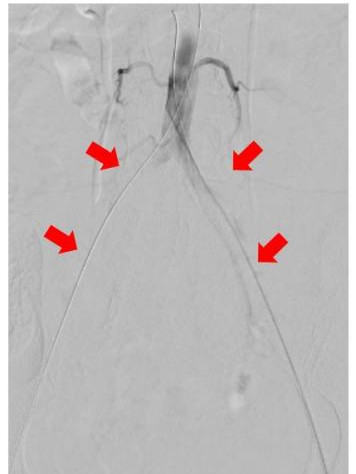

圖中箭頭所示:術(shù)前CTA提示腹主動(dòng)脈雙髂動(dòng)脈騎跨栓,腹主動(dòng)脈下段及雙髂動(dòng)脈血流中斷

術(shù)中DSA:箭頭提示雙髂動(dòng)脈血栓栓塞,血流中斷